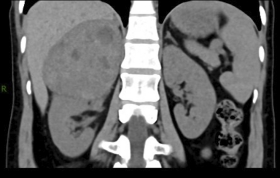

8个多来,谢女士反复胸闷、胸痛、心悸,血压、血糖升高,于2021822日前往市第一人民医院心血管内科住院治疗,头颅、胸部CT检查未见异常。后又腹部增强CT检查,发现右侧肾上腺区见团块状混杂软组织密度影,轮廓清晰,大小约9.5x9.0x9.4cm,CT值约20-40Hu,增强扫描动脉期强化并见多条小血管穿行、囊状未强化影,静脉期呈渐进性强化,下腔静脉推移变窄,右肾受压下移右侧肾上腺区占位经泌尿外科、内分泌科会诊完善相关检查后诊断右肾上腺巨大嗜铬细胞瘤需行手术切除方可根治。

术前CT片